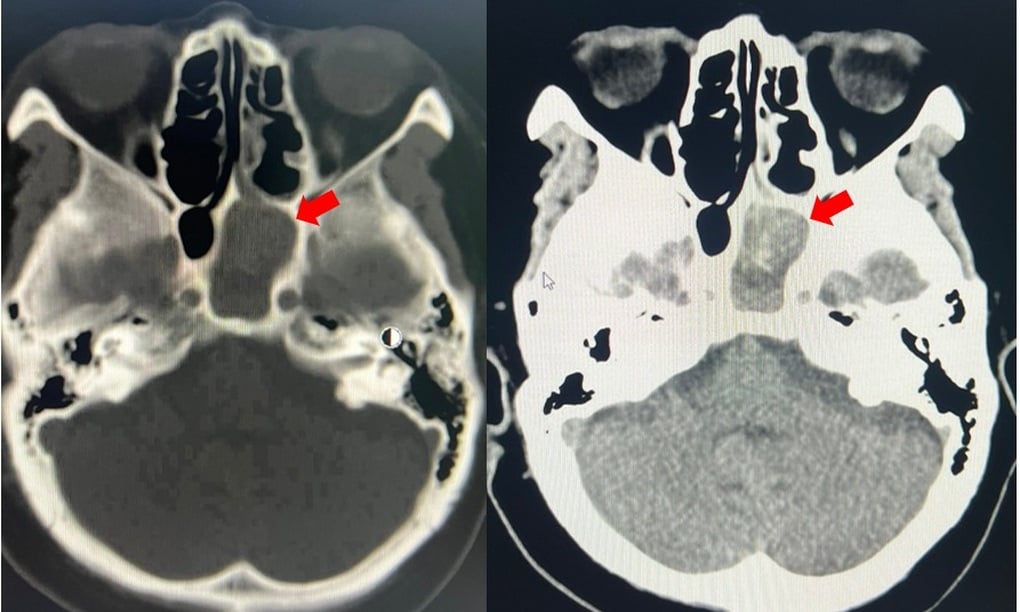

La tomografía computarizada y los resultados paraclínicos posteriores también determinaron que la paciente presentaba sinusitis esfenoidal izquierda causada por un hongo con infección. Además, se observaron diversas enfermedades subyacentes, como hipertensión arterial, enfermedad renal crónica en estadio III y diabetes tipo 2.

Imagen de masa del seno esfenoidal izquierdo (flecha roja) (Foto: Hospital).